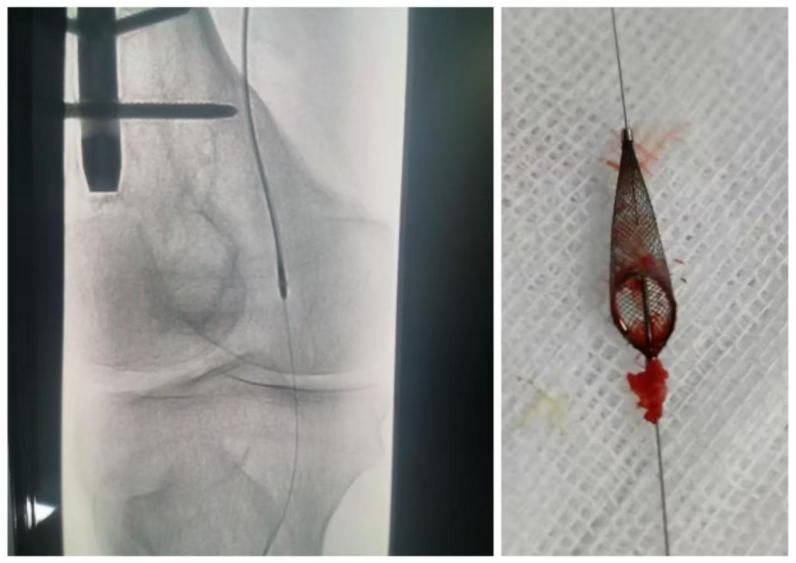

鞠大叔手术更为惊险:血管里的旧支架已经 “生锈”(内膜增生),刀头贴着支架内壁把增生组织一点点磨掉,全程没伤着血管,最后连保护伞里都吸出了一堆 “小碎石”!

传统手术切下的斑块碎屑容易随血流跑到脚里,堵死小血管(栓塞),风险高达 15%-20%。(Jetstream 斑块旋切)一边切一边 “吸走” 碎屑,栓塞风险不到3%,再加上 “保护伞”(像渔网兜住碎屑),风险更低到1%!